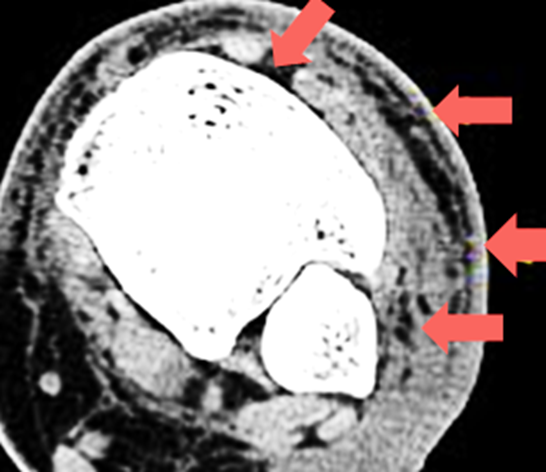

b. MRI

• High sensitivity for soft tissue and bone involvement

• T2-weighted images show:

• Subcutaneous hyperintensity (edema)

• Fascial thickening

• Rule out osteomyelitis or septic arthritis

MRI:

• Cellulitis: Demonstrates diffuse soft tissue edema and enhancement without bone marrow involvement.

• Osteomyelitis: Shows bone marrow edema, cortical destruction, and possible abscess formation.